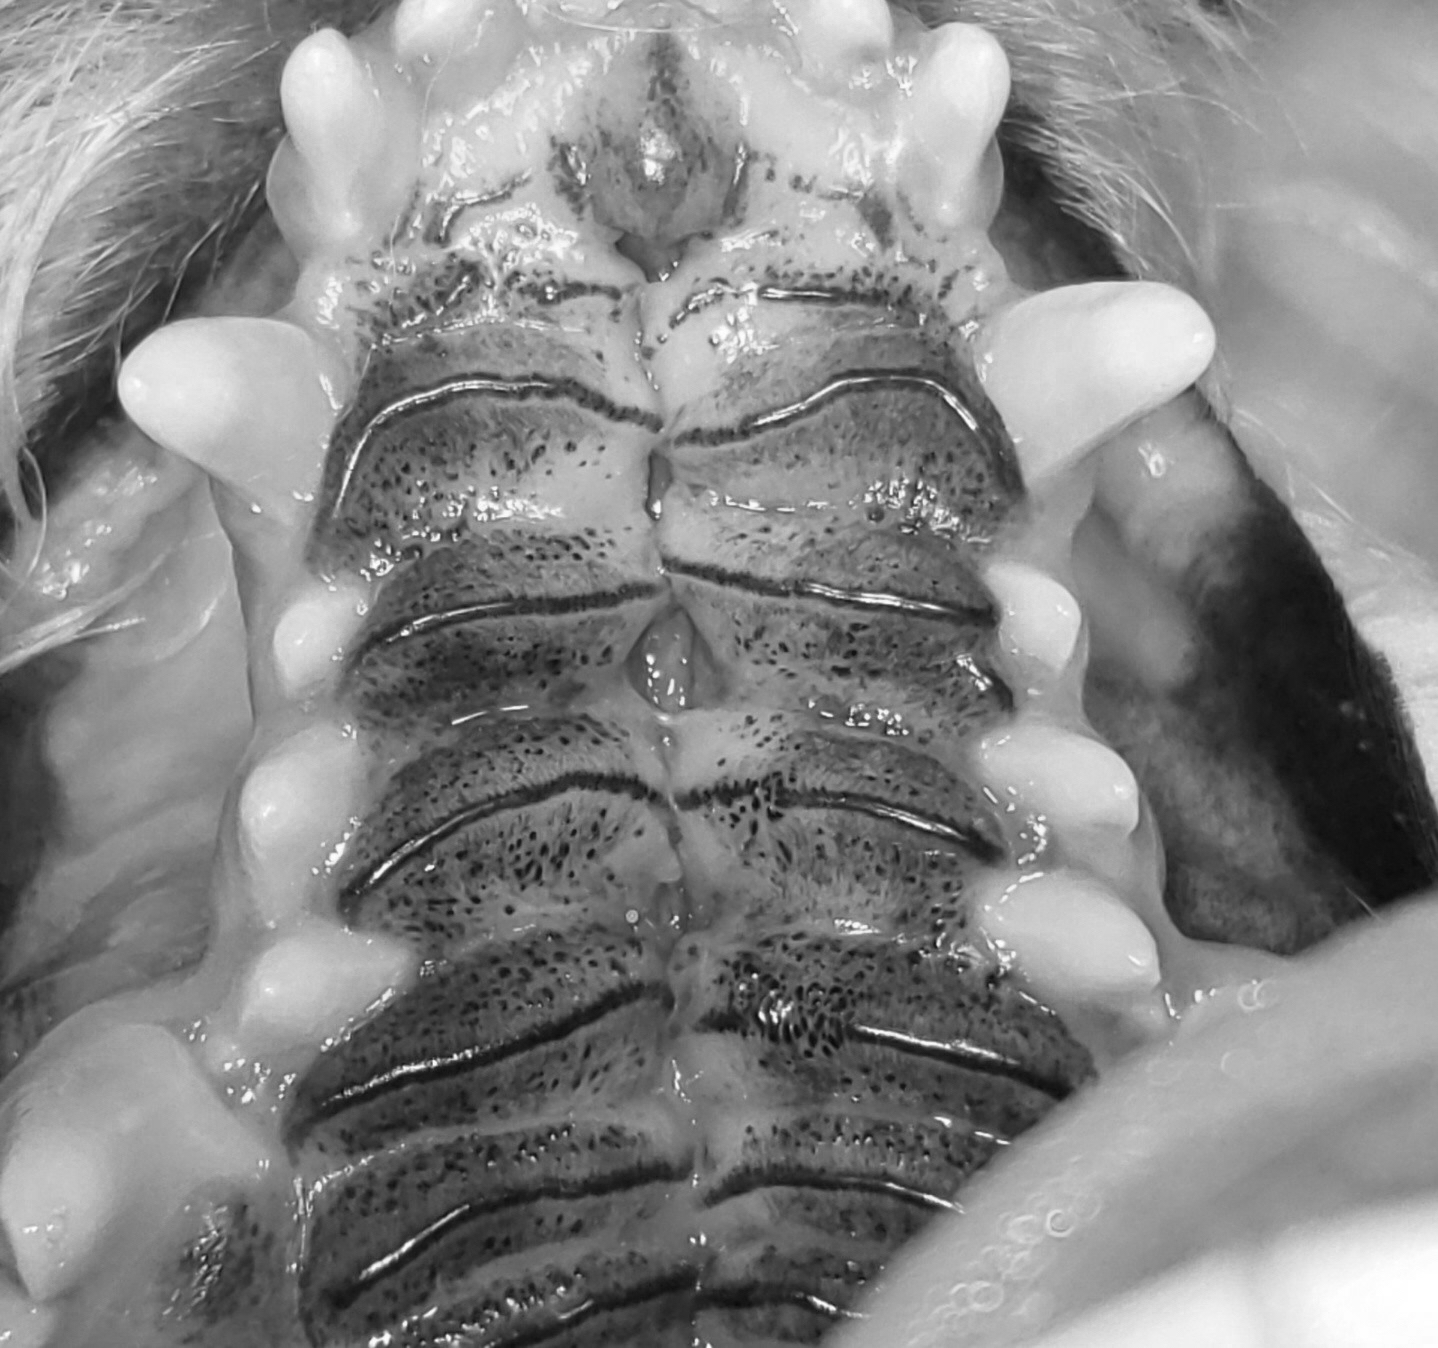

입천장이 비정상적으로 갈라져 있어서 틈새가 생기는 선천적인 기형으로, 태아 발생기에 두 개의 입천장 선반이 정상적으로 융합되지 않아 발생하게 됩니다. 구개열이 있으면 육안으로 입천장에 생긴 구멍인 기형 부위를 확인할 수 있습니다.

심바의 경우 경구개와 연구개 모두 결손부위가 발생했는데, 경구개 부위는 flap을 형성하여 결손부를 덮어주고, 연구개 부위는 봉합을 통해 결손부를 폐쇄해주는 수술을 진행했습니다. 또한 수술 후 음식물에 의한 비강 내 오염과 오연성 폐렴을 방지하기 위해 식도관을 장착해주었습니다.